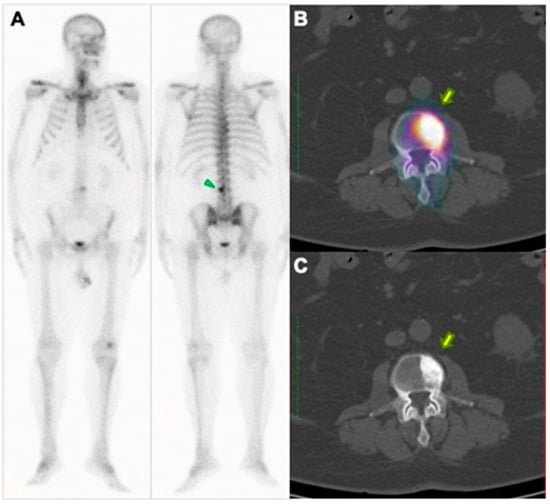

3.2. Diagnosis with PET/CT with 18F-Fluoride

3.3. Treatment with Radium-223